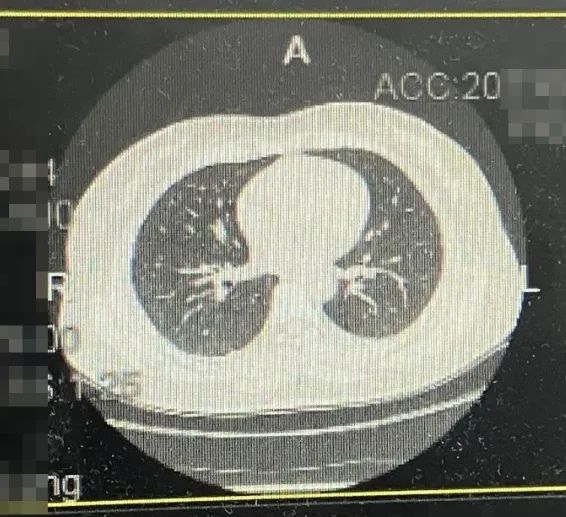

·乳腺钼靶

1、双乳腺体密度混合型ACR c型;

2、双乳小叶增生伴瘤化;右乳外上象限多发结节,考虑BIRADS 4B类,建议进一步MR检查。

图2乳腺DR结果